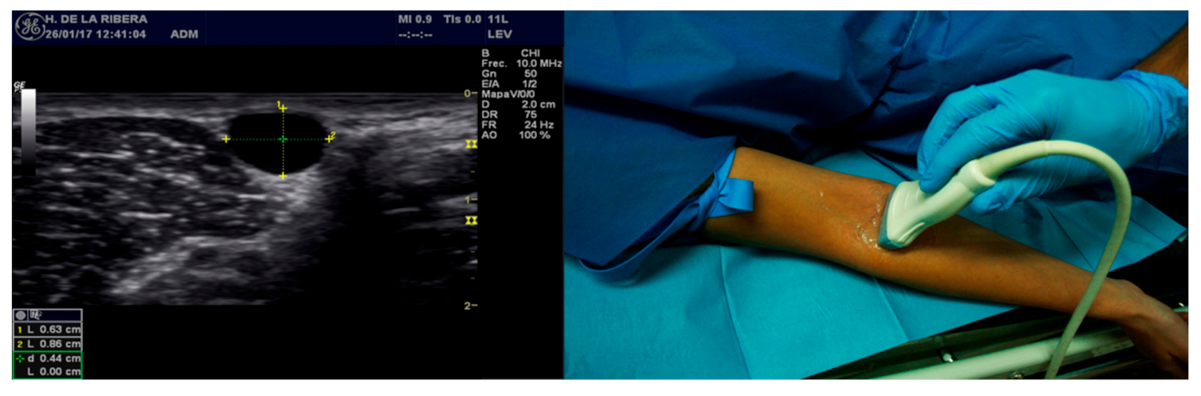

2.3. Equipment